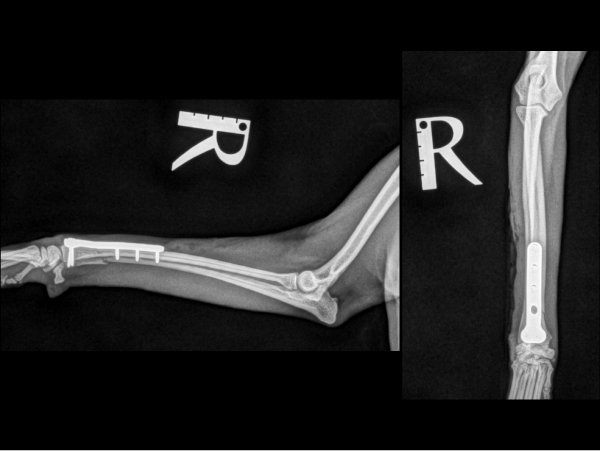

<術前のレントゲン>

右橈尺骨遠位端が骨折しています。

<術後のレントゲン>

インプラントによる内固定を行いました。